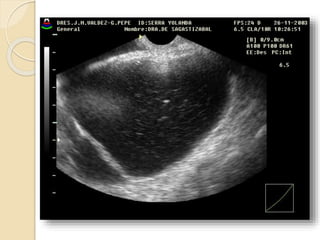

Poliquistosis Ovárica:

Se describe este síndrome como cambios

escleroquísticos en el ovario, mas

amenorrea, infertilidad e hirsutismo.

Ecográficamente vamos a ver

agrandamiento de ambos ovarios con

quistes subcorticales de menos de 1cm.,

mas incremento de las dimensiones del

estroma y fibrosis subcapsular.